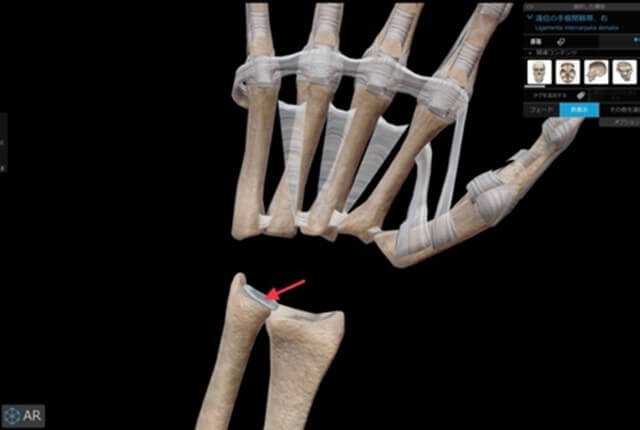

TFCC縫合術

DRUJ不安定性高度のTFCC損傷は尺骨遠位に縫合する手術法があります。